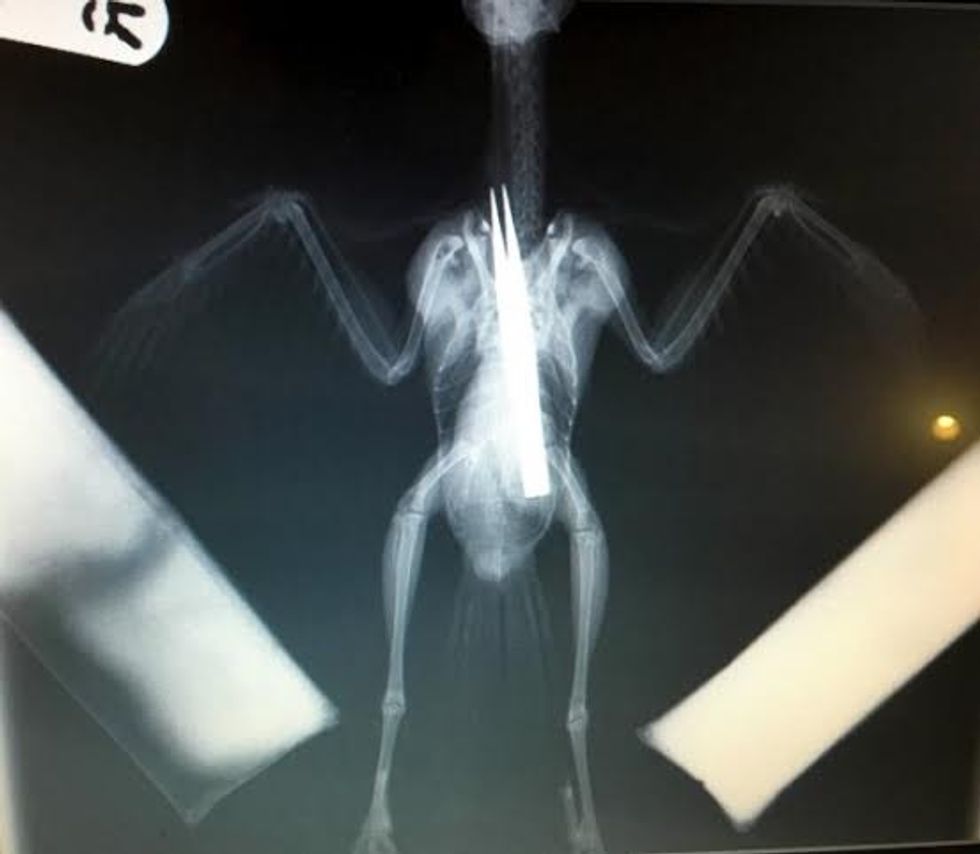

705:"PIC FROM CATERS NEWS - (PICTURED: The Jackdaw) - A young bird that swallowed a pair of TWEEZERS was saved after quick-thinking vets plucked them from him stomach. The greedy jackdaw wolfed down the metal tongs which x-rays revealed had stretched the full length of his body. Vets were concerned that the internal damage caused to the young bird would be too great but following a delicate hour-long procedure the jackdaw from Swadlincote, Derbyshire, is now on the mend. Wildlife vet Dr Bev Panto from RSPCA Stapeley Grange Wildlife Centre said: When I saw the x-rays and the size of the tweezers he had swallowed, I thought there was absolutely no chance this poor jackdaw could survive. SEE CATERS COPY.

Një zog i vogël që ngjan më së shumti me sorrën, ia ka dalë të përpijë një palë pinca që janë të gjata sa trupi tij.

Shpendi i njohur si shumë kureshtar, është zbuluar se ka një palë kapëse metalike, pasi veterinerët e kanë fotografuar me anë të rrezeve X, transmeton Telegrafi.

Nuk dihet se si e ka përpirë zogu i zi këtë pajisje metalike, që ka maja shumë të mprehta dhe se si nuk është lënduar.